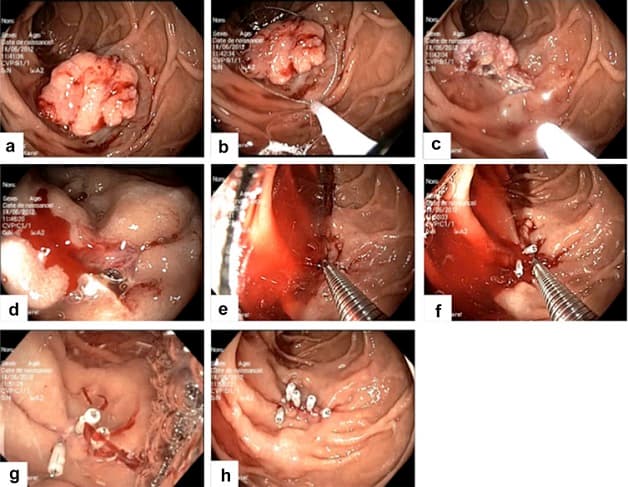

Bác sĩ có thể sử dụng các dụng cụ đặc biệt để sinh thiết, cắt polyp, cầm máu, lấy dị vật, thắt tĩnh mạch thực quản, nong những phần bị hẹp,… trong quá trình nội soi.

Nội soi dạ dày qua đường miệng có thể thực hiện các thủ thuật can thiệp như sinh thiết, lấy dị vật, cầm máu,…

– Bác sĩ có thể thực hiện các thủ thuật can thiệp (lấy dị vật, cầm máu, cắt polyp, tiêm xơ, nong hẹp, thắt tĩnh mạch thực quản) thuận lợi và an toàn hơn.